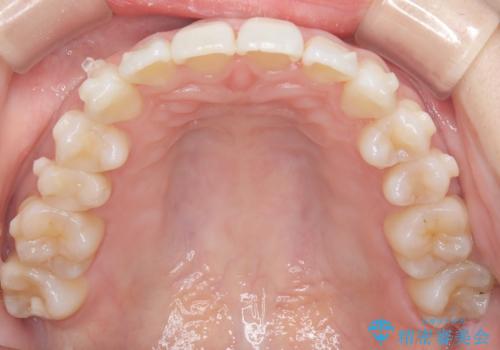

インビザラインモデレートによる前歯の叢生改善|IPR最小限で自然な歯並びへ

診査の結果、中等度の叢生であったため、インビザラインモデレートでの対応が可能と判断しました。

歯へのダメージを抑えるため、IPR(歯間削合)は必要最小限にとどめる方針としました。

前歯の叢生は解消され、自然で調和の取れた歯並びが得られました。

「歯をほとんど削らずにきれいになった」と、患者様にもご満足いただけました。